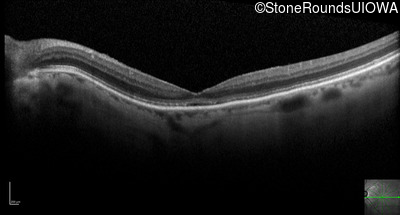

Optical Coherence Tomography - Right - 20/250

Exemplar / OCT Stack

OCT Stack